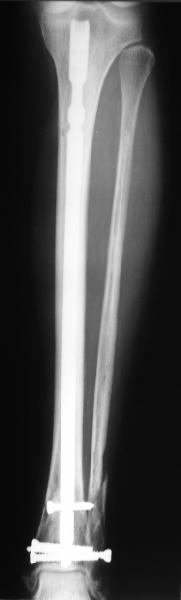

A typical case is attached, also an image with intra-op reduction obtained by a small wire distractor, in the moment of insertion a Poller wire in AP direction. Fixation by a SIGN nail. Despite the fibula was not fixed healing was obtained with the unchanged alignment.

Very interesting application, but is the final position in a little distal varus with some fibula

distraction? Would that have been eliminated by fibula plating?

TDVC> Very interesting application, but is the final position in a

TDVC> little distal varus with some fibula distraction?

At least both the ankle mortise and tibial alignment look acceptable, don't they?

TDVC> Would that have been eliminated by fibula plating?

I am just trying to illustrate that prevention of 1)tibial valgus and 2)loss of reduction can be provided without fibular plating. Small changes of conventional nailing techniques allow to maintain reduction of the tibia reliably without adjunctive fibular stabilization.